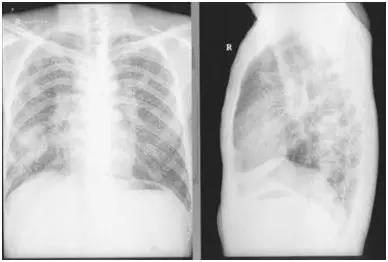

曾先生的X线胸片:两肺布满斑块状不均质阴影,提示肺炎症和纤维化

我看了曾先生的胸片。片子拍的质量不太好,但清楚显示两肺上中下三个肺区有大小不等斑块状影,以右侧中下肺区为多,密集度3级,可诊断为三期尘肺(Ⅲ)。曾先生儿子说:“这是近期拍的片子,以前的要严重得多,两肺都是班班块块,好吓人!”